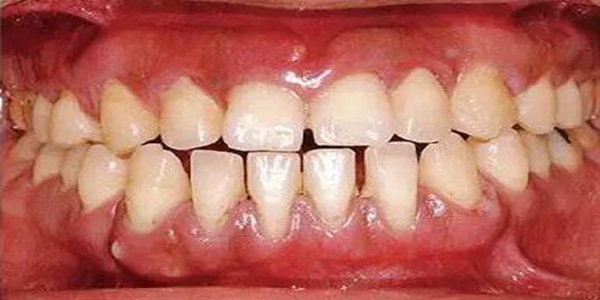

●健康且正常的牙周組織臨床圖像

●參考病例① 35歲女性

35歲女性。妊娠4個(gè)月。過(guò)去雖然接受過(guò)刷牙指導(dǎo),但菌斑控制狀態(tài)依然不理想?;颊哂邪l(fā)現(xiàn)自己刷牙時(shí)牙齦出血。

●參考病例② 25歲女性

25歲女性。菌斑控制狀態(tài)不好。齦溝除磨牙處外全在3mm以下,X光照片上左上、右下、左下的第一磨牙上有垂直性骨吸收。這個(gè)病例是參考病例①10年前的狀態(tài),是典型的侵襲性牙周炎局部型。